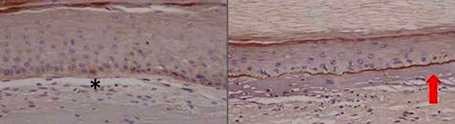

Fanconi anemia patients are at very high risk of developing squamous cell carcinoma of the head and neck (SCC and C). In addition, the disease occurs at a very young age and treatments are not effective. Therefore, new treatments are needed for this population at risk. Researchers from CIEMAT, Instituto de Investigación Hospital 12 Octubre, CIBERONC, CIBERER and IIS-FJD have created new cell models that will allow the search for more effective therapies in these patients. The results have been published in the journal Genes. For more information, consult the following news:

New models of head and neck cancer in Fanconi Anemia patients

New models of head and neck cancer in Fanconi Anemia patients. Fanconi anemia patients are at very high risk of developing squamous cell carcinoma of the head and neck (SCC and C). In...